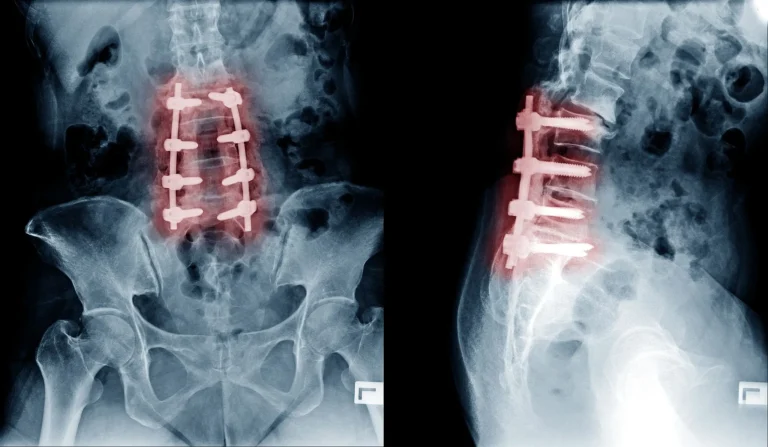

X-ray showing spinal fusion with metal implants in the lumbar region, both front and side views.

Back Pain Gets Worse

X-ray showing spinal fusion with metal screws and rods in the lower back.

Additional Surgery Likely Needed

MRI of the spine showing bone slip due to post-surgical instability, indicated by red arrows.

Spinal Instability

Bone destruction from the procedure causes vertebral instability requiring fusion with screws and rods.